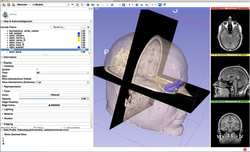

Slicer4Minute Tutorial

- The Slicer4Minute tutorial is a brief introduction to the advanced 3D visualization capabilities of Slicer 4.5.

- Author: Sonia Pujol, Ph.D.

- Audience: First time users who want to discover Slicer in 4 minutes.

- Modules: Welcome to Slicer, Models

- Based on: 3D Slicer version 4.5

- The Slicer4Minute dataset contains an MR scan of the brain and 3D models of the head.